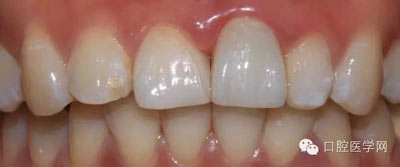

6、術(shù)后一周照,牙齦恢復(fù)良好

7、術(shù)后照飽和度調(diào)到最低與最高,觀察牙齒修復(fù)后的明度及飽和度